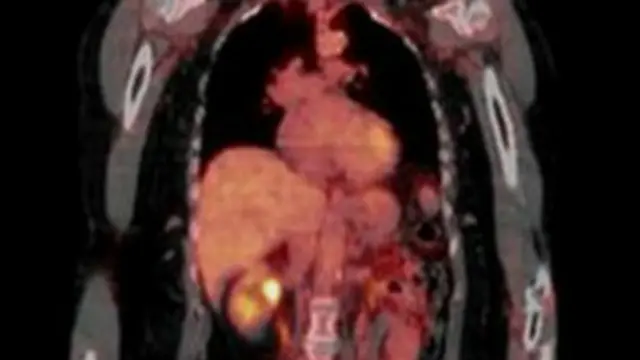

ब्रितानी वैज्ञानिक फेफड़े के कैंसर से पीड़ित 850 लोगों के ट्यूमर का अध्ययन करेंगे ताकि इस प्राणघातक बीमारी के बारे में ज़्यादा जानकारी हासिल हो सके.

इस शोध में यह पता किया जाएगा कि कैंसर पीड़ित पर उपचार का असर होना क्यों बंद हो जाता है.

इस अध्ययन में यह भी पता लगाया जाएगा कि पिछले नौ सालों के दौरान फेफड़े का <link type="page"><caption> कैंसर</caption><url href="http://www.bbc.co.uk/hindi/science/2013/07/130718_cancer_sinffing_knife_vt.shtml" platform="highweb"/></link> किस तरह विकसित हुआ और फैला.

इंग्लैंड में हर साल फेफड़े के कैंसर के 42,000 नए मामले सामने आते हैं और इनमें से 35,000 की मौत हो जाती है.

पिछले पाँच सालों में फेफड़े के कैंसर से पीड़ित सिर्फ़ 9 प्रतिशत मरीजों की ही जान बचाई जा सकी है.